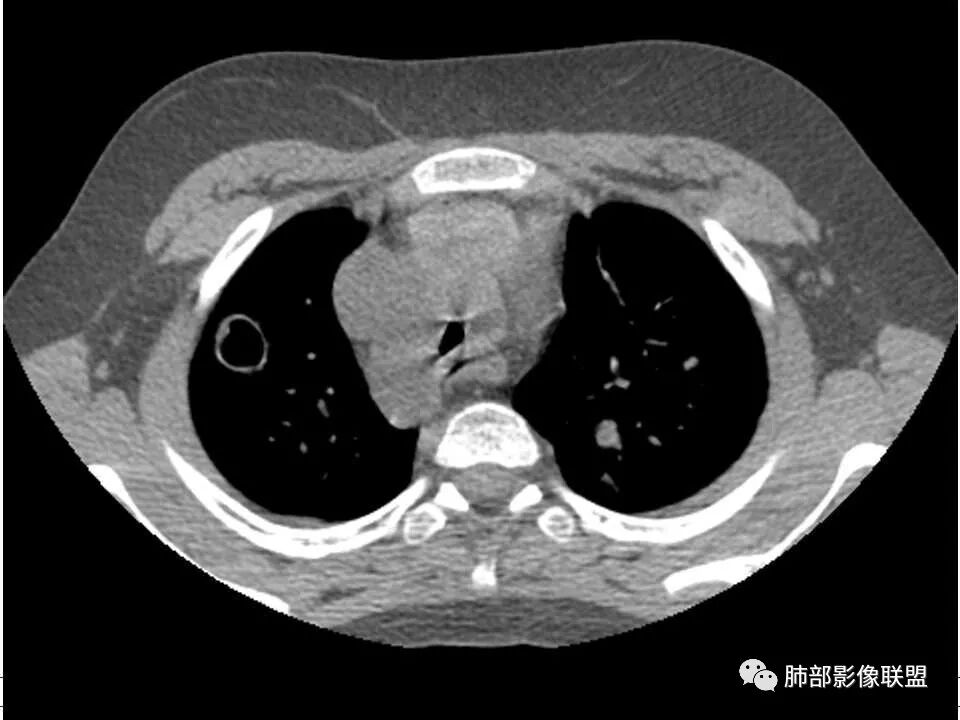

患者儿童,因右下肢疼痛伴肿胀14天就诊。病程中有发热及伴随症状。膝关节MRI提示右侧膝关节及右髌骨髁异常信号影,右膝髌上囊及关节腔内少量积液。胸部CT:双肺胸膜下多发结节影,部分结节空洞形成,且结节周围可见血管集束征。综合考虑血源性脓毒性肺栓塞、坏死性肺炎。右侧骨髓炎、血播性金葡菌肺炎,鉴别其他特殊感染及血管炎。

发热,下肢肿胀骨髓水肿,骨髓炎可能;双肺多发结节,部分空洞,左下肺胸膜下楔形阴影,考虑感染性病变,肺梗死;上腔静脉、奇静脉增宽,肝大,考虑股部深静脉拴子进入体循环及肺动脉,综上考虑下肢骨髓炎,深静脉脓毒栓子,肺部感染并肺栓塞

2.双肺多发片影,随机分布,多空洞或囊腔,胸膜下多楔形影,气道未见受累等等符合脓毒血症影像学表现,尤其是金葡。

2、脓肿:实变区内脓肿,最常见吸入性金葡菌引起的多,下叶多见,在实变区中央,外壁不清,内壁光滑,可见气液平面;血源性脓肿,多发,结节状,大小无差异,边清,光滑,壁薄;

1. 多发胸膜下外周结节、< 3 cm 的楔形影和滋养血管征 CT 表现;